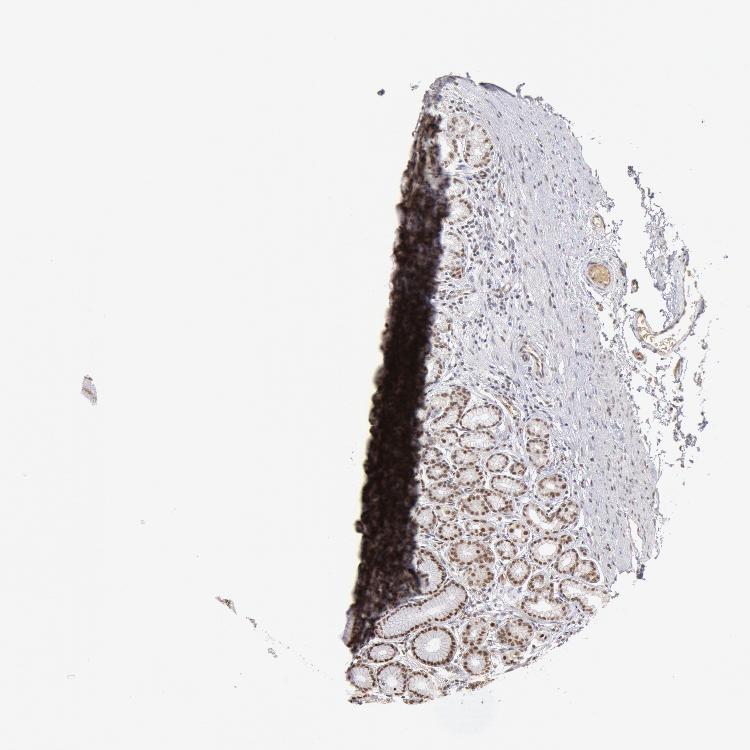

TISSUE PRIMARY DATA STOMACH Show tissue menu

STOMACH 1 - Antibody stainingi

Antibody staining in the annotated cell types in the current human tissue is reported as not detected, low, medium, or high, based on conventional immunohistochemistry profiling in selected tissues. This score is based on the combination of the staining intensity and fraction of stained cells.

Each image is clickable and will lead to virtual microscopy that enables deeper exploration of all samples and also displays staining intensity scores, fraction scores and subcellular localization as well as patient and tissue information for each sample.

Antibody HPA001233Antibody CAB017185

Glandular cells MediumHigh